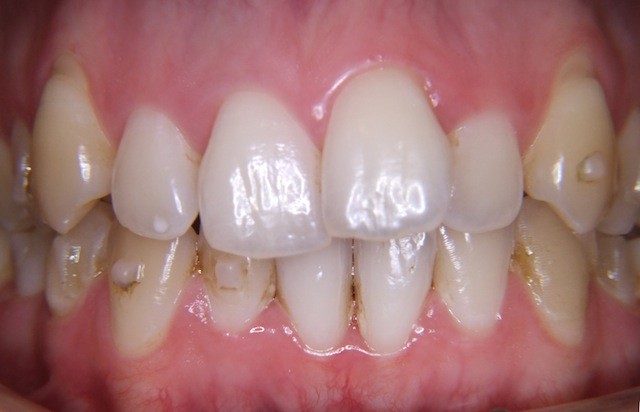

Vorher ----------------------------------- Nachher

Bilderserie Invisalignbehandlung Oberkiefer mit Stabilisierungsdraht am Schluss. Man beachte die Ansammlung von Belägen und Verfärbungen infolge Nischenbildung am Zahn der am meisten im Engstand steht.